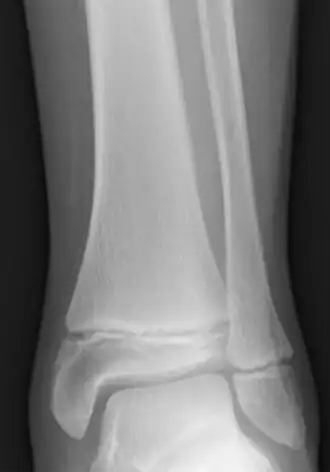

Radiogram of distal tibia (left) and fibula (right) showing two epiphyseal plates

The plate is only found in children and adolescents; in adults, who have stopped growing, the plate is replaced by an epiphyseal line. This replacement is known as epiphyseal closure or growth plate fusion. Complete fusion can occur as early as 12 for girls (with the most common being 14–15 years for girls) and as early as 14 for boys (with the most common being 15–17 years for boys).[1][2][3][4][5]